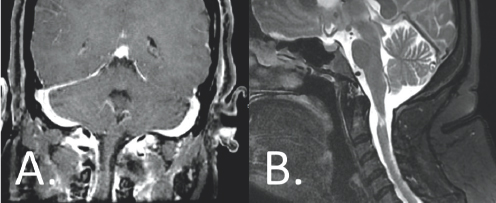

In the emergency department, MRI scans of Isabella’s brain and cervical spine were obtained. MRI of the cervical spine revealed a large tumor near the craniocervical junction resulting in severe impingement of her spinal cord (Figure 4.1). The source of her progressive neurologic disability had been identified. Based on its appearance on the MRI, the radiologist suspected the tumor was of peripheral nerve sheath origin

(Right) A large sized white blob is shown attached to a grey vertical column. A yellow arrow points to this white blob. Both structures are surrounded by other gray structures. (Right) A white spherical blob is highlighted by a yellow arrow. This blob is located in the center of the image overlapping a light gray colored column. These structures are surrounded by other gray and white structures.

FIGURE 4.1 Coronal, T1-weighted, post-contrast (A) and sagittal, T2-weighted (B) imaging demonstrated a large extramedullary tumor (yellow arrows), resulting in severe impingement of the high cervical spinal cord.